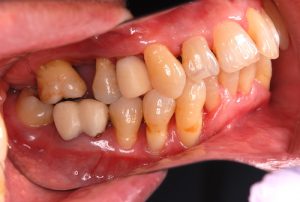

この方は上の奥歯が無い状態が長期間続いたため、奥歯が傾いてしまい歯が入れられない状態でした。

また歯が傾いていることで、プラークがたまりやすく実際に歯周病を発症していました。

そこで、傾いた歯を元に戻し、隙間にきちんと歯が入るように矯正治療を行うことにしました。